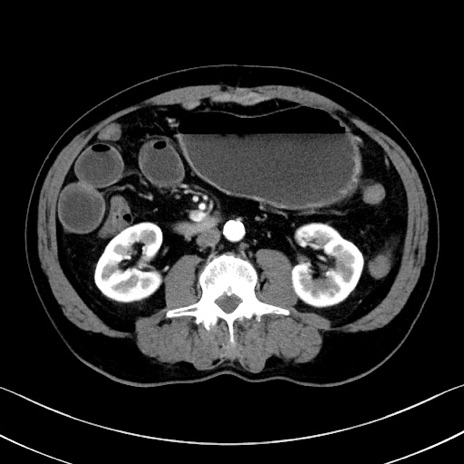

症例35(横断像)

【症例】70歳代 男性

【主訴】腹部膨満、嘔吐

【現病歴】昨日より腹部膨満感出現。本日増悪し、仙痛出現。嘔吐あり、受診。

【既往歴】糖尿病、胆摘後

【身体所見】BP 149/80mmHg、HR 74/min、BT 35.9℃、腹部:膨満、軟、圧痛なし。腸雑音減弱あり。上腹部正中切開瘢痕あり。

【データ】WBC 13500、CRP 1.72